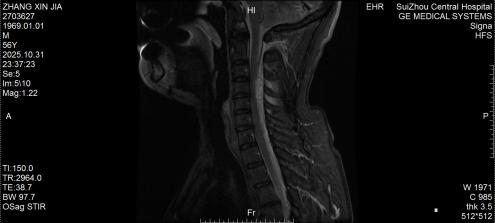

10月底的深夜,隨州市中心醫(yī)院急診醫(yī)學(xué)科來(lái)了一位特殊患者,突發(fā)劇烈頸痛伴雙手麻木,短短3小時(shí)內(nèi)肢體無(wú)力逐漸加重,連簡(jiǎn)單抬臂都難以完成。脊柱外科團(tuán)隊(duì)緊急評(píng)估后行頸椎磁共振檢查,確診為自發(fā)性頸椎椎管內(nèi)出血—— 這是今年該院救治的第5例同類患者。好在急診手術(shù)及時(shí)清除血腫、解除神經(jīng)壓迫,患者術(shù)后恢復(fù)良好,無(wú)任何后遺癥,順利出院。

圖1:術(shù)前MRI見椎管內(nèi)積血壓迫脊髓

圖2:術(shù)后MRI見脊髓壓迫解除